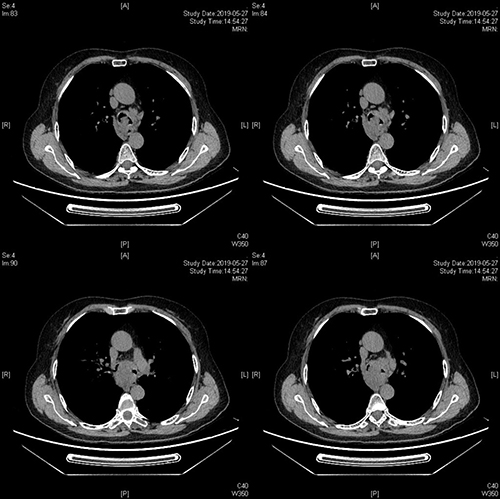

5月27日下午14:00,一名大气道95%狭窄的高危病人,搭乘外地120急救车慕名来到我院呼吸与危重症医学科姜淑娟专家门诊就诊,经初诊后,由于情况紧急,立即通过绿色通道办理入院,并同时安排复查胸部CT了解病情。

经进一步检查发现,该患者大气道狭窄95%,病人随时可能因为痰液窒息而亡!